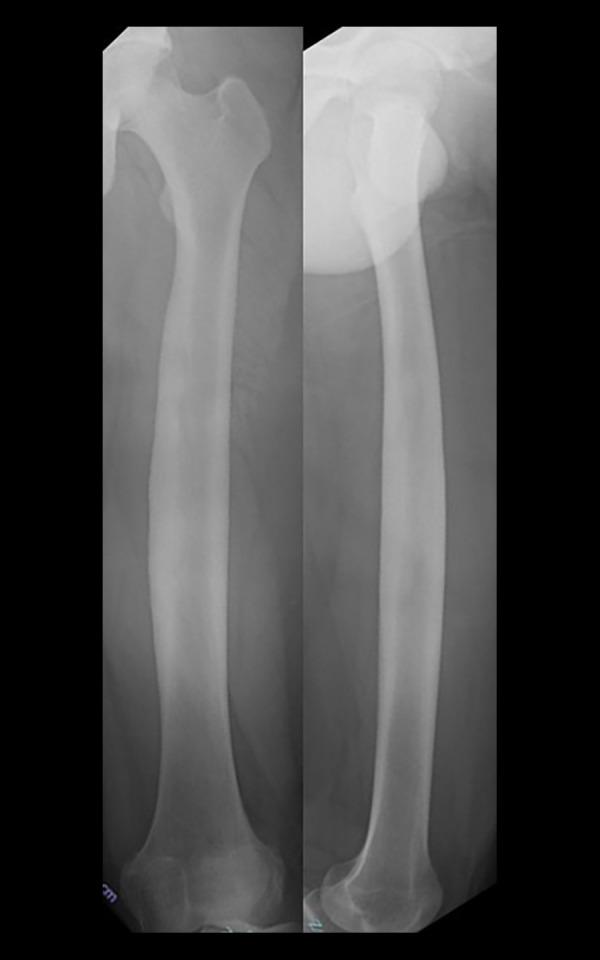

BACKGROUND Brodie's abscess is a rare form of subacute osteomyelitis that primarily affects the metaphyseal regions of long bones. Conventional treatment involves thorough curettage and systemic antibiotic therapy for ≥6 weeks, with bone grafting required for abscess sizes >3 cm. Continuous local antibiotic perfusion (CLAP) delivers high concentrations of antibiotics directly to the infection site and facilitates preservation of biologically active bone tissue. Here, we report a case of an extensive Brodie's abscess that was successfully treated with CLAP, highlighting its potential as an alternative to conventional treatment. CASE REPORT A 14-year-old boy was diagnosed with a 15-cm Brodie's abscess in the medial cortical bone of the left femur, with a primary infection in the intracortical pseudocavity. The patient underwent treatment with CLAP and intramedullary antibiotic perfusion pins were placed in the pseudocavity. Given the preservation of bone bioactivity, we anticipated spontaneous bone remodeling after infection control and therefore decided against bone grafting. The infection site received direct gentamicin infusions for 18 days, and systemic antibiotic therapy continued for 1 month. Postoperatively, the signs of inflammation rapidly subsided, and thereafter, no recurrence of infection was observed, while bone remodeling was achieved at the site of the bone defect. CONCLUSIONS In cases of cortical bone abscess, systemically administered antibiotics have limited penetration, whereas CLAP allows direct administration of high-concentration antibiotics to the lesion, which may provide an advantage in infection control. The findings of this case suggest that CLAP may serve as a viable treatment option for Brodie's abscess, particularly in cases with limited systemic antibiotic penetration.

布罗迪脓肿是亚急性骨髓炎的一种罕见形式,主要影响长骨的干骺端区域。传统治疗包括彻底刮除和≥6周的全身抗生素治疗,脓肿大小>3 cm时需要进行骨移植。持续局部抗生素灌注(CLAP)可将高浓度抗生素直接输送到感染部位,并有助于保留具有生物活性的骨组织。在此,我们报告一例广泛的布罗迪脓肿病例,该病例通过CLAP成功治疗,突出了其作为传统治疗替代方法的潜力。病例报告:一名14岁男孩被诊断出左股骨内侧皮质骨有一个15 cm的布罗迪脓肿,皮质内假腔内存在原发性感染。患者接受了CLAP治疗,并在假腔内放置了髓内抗生素灌注针。鉴于骨生物活性得以保留,我们预计感染控制后会发生自发性骨重塑,因此决定不进行骨移植。感染部位接受了18天的庆大霉素直接输注,全身抗生素治疗持续了1个月。术后,炎症迹象迅速消退,此后未观察到感染复发,同时在骨缺损部位实现了骨重塑。结论:在皮质骨脓肿病例中,全身应用抗生素的穿透性有限,而CLAP可将高浓度抗生素直接应用于病变部位,这在感染控制方面可能具有优势。该病例的结果表明,CLAP可能是布罗迪脓肿的一种可行治疗选择,特别是在全身抗生素穿透性有限的情况下。